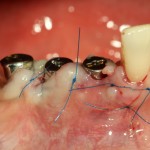

Делаем разрез по зубодесневой борозде. На фотографии видно как точку перфорации (в поднадкостничное вестибулярное пространство, так и наличие в нем распада некротизированных тканей вперемежку с материалом для обработки каналов:

Аккуратно промываем рану физраствором, удаляем все ее содержимое. На левой фотографии хорошо заметна как сама перфорация корня и вестибулярной стенки костной ткани, так и ожог надкостницы, вызванный медикаментами для обработки каналов.

После этого аккуратно удаляем зубы.

На фотографиях ниже видно, как выглядят лунки зубов после удаления: тонкие, почти прозрачные вестибулярные стенки при сохраненной высоте альвеолярного гребня.

Готовим лунки под импланты Friadent Xive. В область резца установлен имплантат диаметром 3,0 мм, в область клыка — 3,4 мм. Обратите внимание на позиционирование имплантов в лунках — смещение язычно и небольшая девергенция. Подобное положение связано с анатомическими особенностями данной области.

Подобным позиционированием и подбором имплантов удалось добиться качественной стабилизации. Мы удаляем имплантодержатели, еще раз проверяем их положение и (особенно!) глубину погружения в лунки.

На импланты устанавливаются формирователи десны, а на слизистую накладываются швы. Для операций имплантации я использую, исключительно, нерезорбируемый шовный материал. В данном случае — Prolene 6-0.